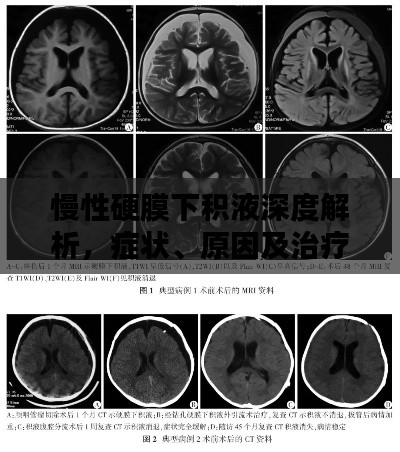

慢性硬膜下积液深度解析,症状、原因及治疗方法

在医学领域中,慢性硬膜下积液是一个相对常见的病症,本文将通过百度搜索,为您详细解析这一病症的相关知识。慢性硬膜下积液概述慢性硬膜下积液是指在硬脑膜下腔出现液体聚集的现象,这种病症通常表现为头痛、恶心、呕吐等症状,慢性...